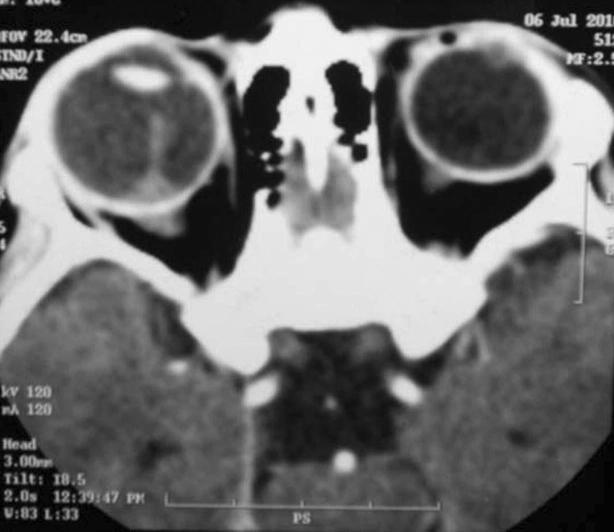

A previously diagnosed child of persistent hyperplastic primary vitreous (PHPV) with painless blind eye remained clinically silent for about 3 years follow-up. The child suddenly presented as a case of orbital cellulitis and panopthalmitis with meningitis. No definite mass lesion was detected on ultrasonography, magnetic resonance imaging (MRI) and positron emission tomography (PET) scan. Histopathology of the enucleated eye revealed intra-ocular medulloepithelioma as the culprit of sterile panophthalmitis and orbital inflammation.

一名先前被诊断为持续性增生性原发性玻璃体(PHPV)的儿童,患眼无痛且失明,在约3年的随访期内临床症状无变化。该儿童突然出现眼眶蜂窝织炎、全眼球炎并伴有脑膜炎的症状。超声检查、磁共振成像(MRI)和正电子发射断层扫描(PET)均未发现明确的肿块病变。摘除眼球的组织病理学检查显示,眼内髓上皮瘤是无菌性全眼球炎和眼眶炎症的病因。